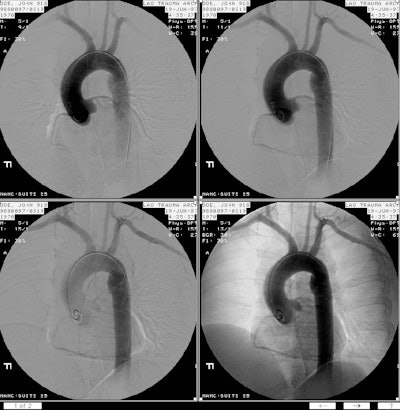

An angiogram demonstrated the channel between the true and false lumens (arrow)